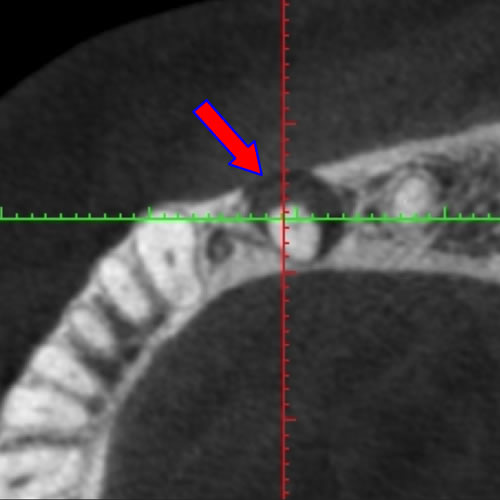

原因は赤の矢印が指す、根の周りの病巣でした。

治療後は青い矢印が指す場所には、黒い病巣が消失しています。

| 治療説明 | 自覚症状で歯が浮いた感じがしていました。上顎大臼歯・頬側根の根尖部にX線透過像の病巣があります。根充剤を除去・拡大清掃・根管充填を行いました。根尖から根充剤がはみ出ていますが、根尖部のX線透過像は見られなくなりました。そこ後、自覚症状もなくなりました。 |

|---|---|